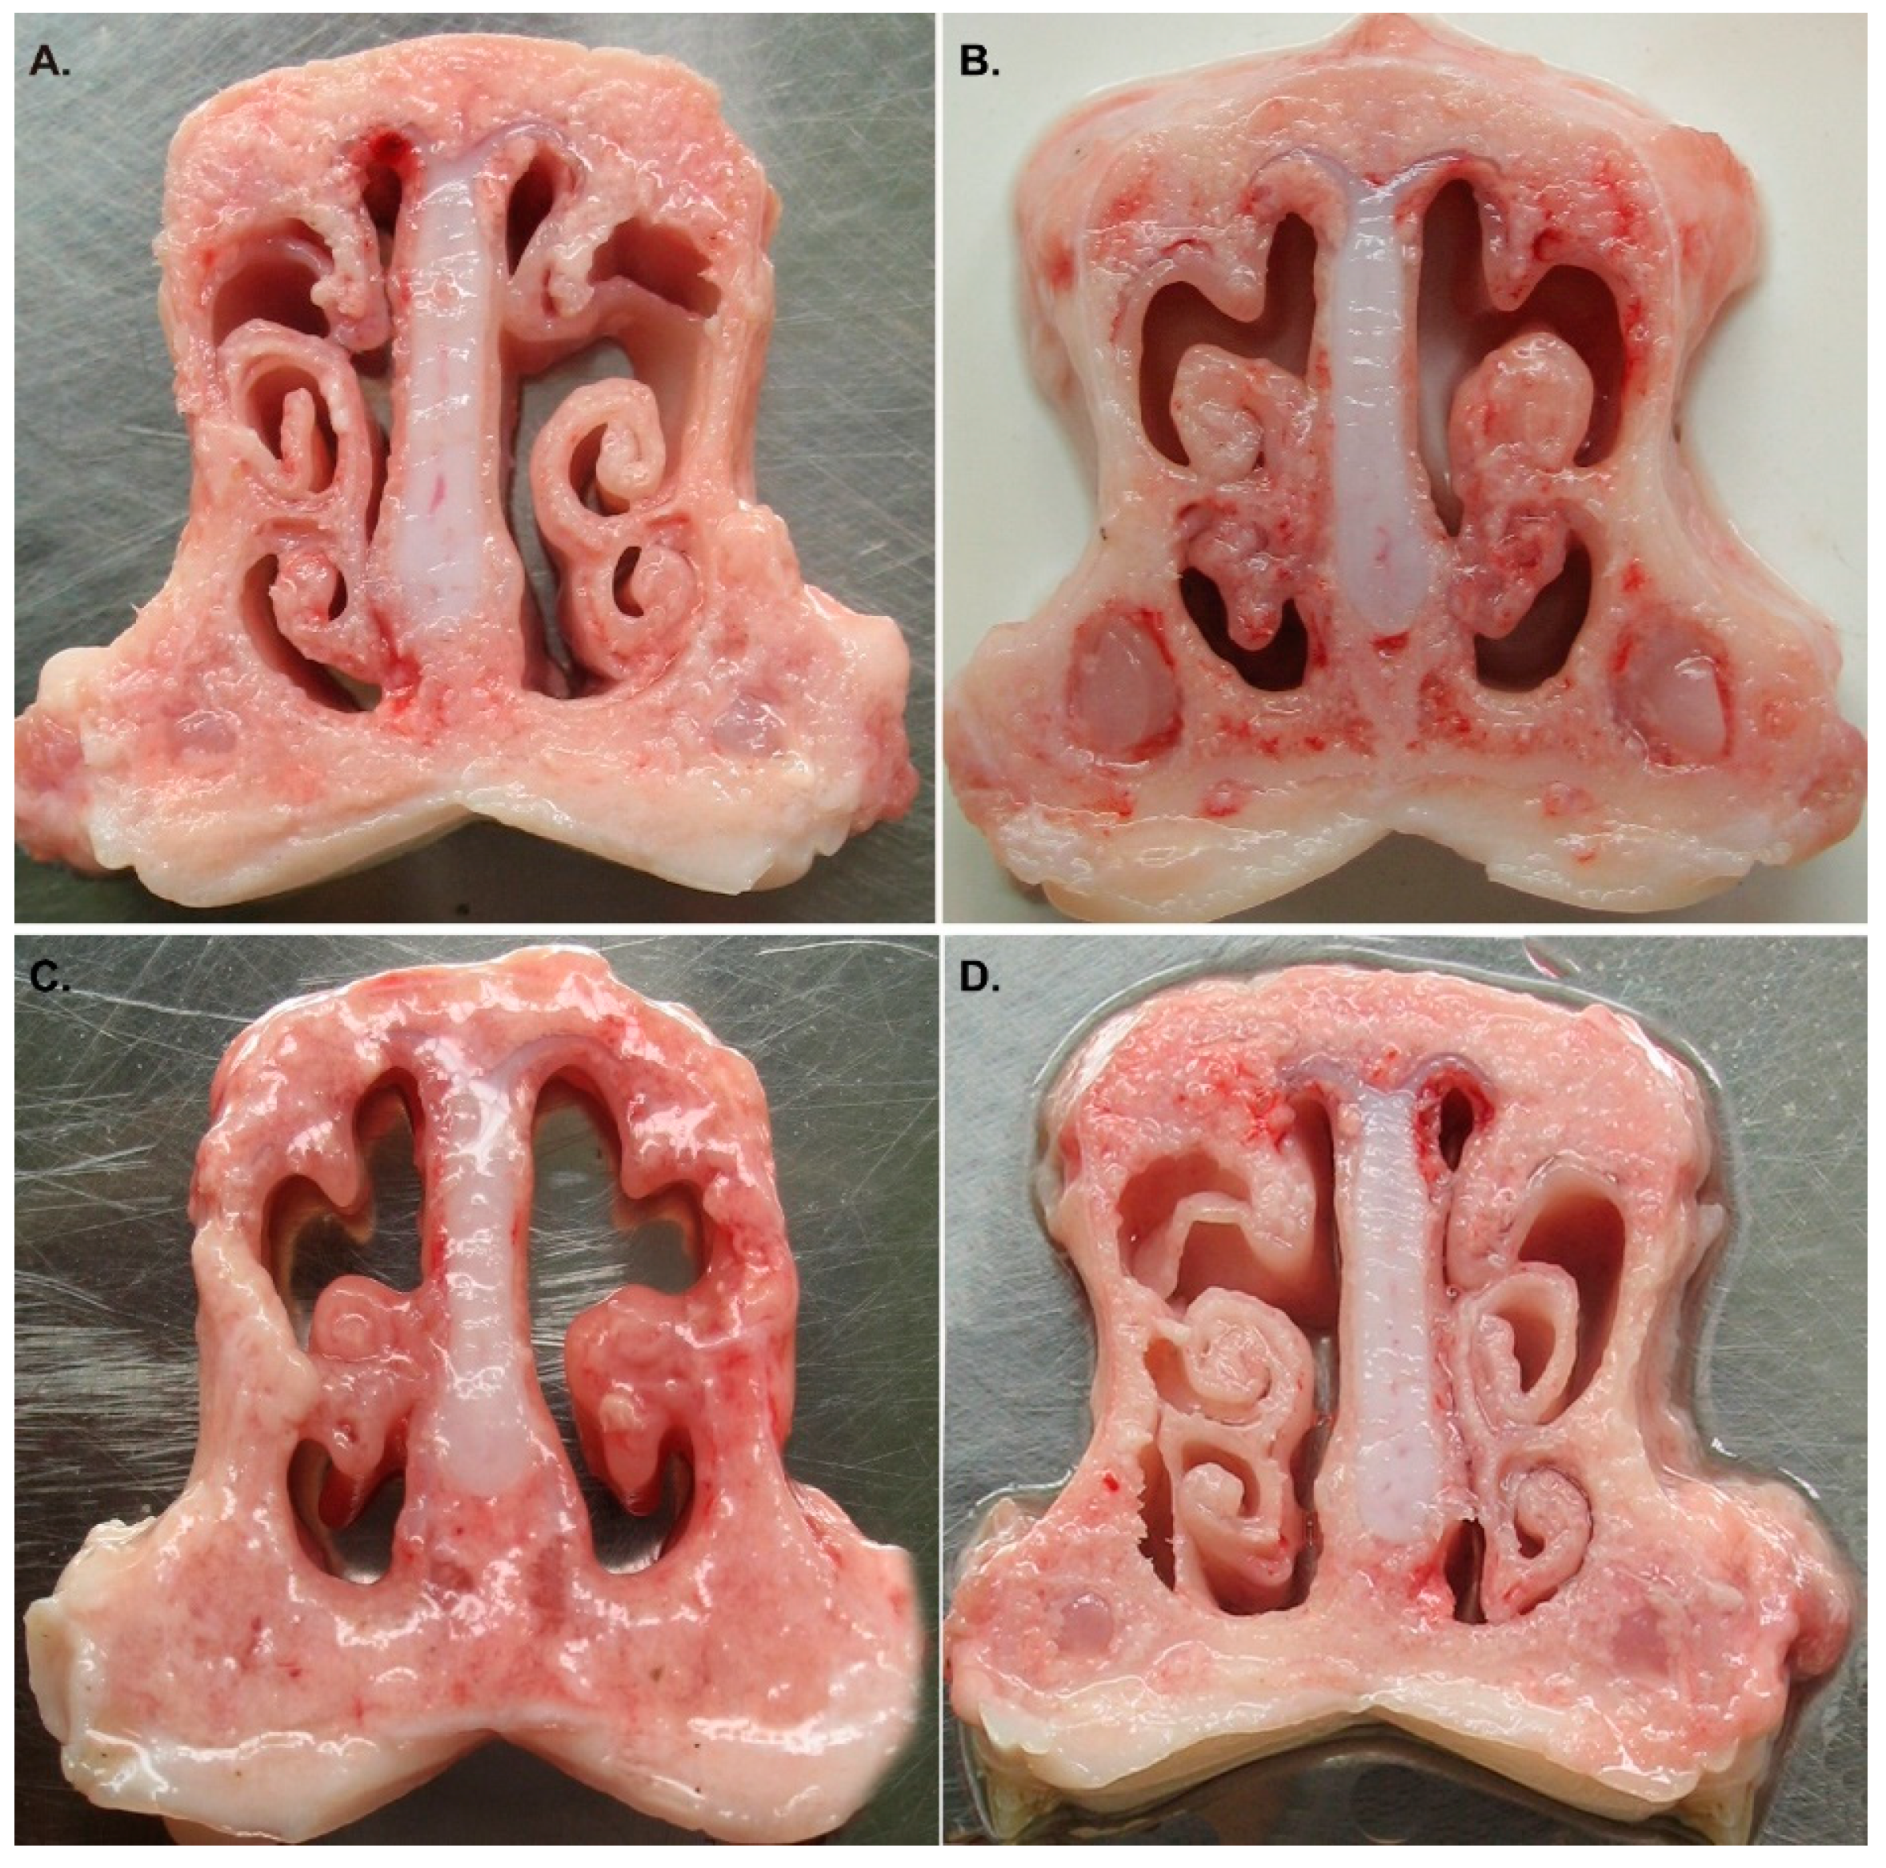

3.3. QH09 Was Safe to Piglets

3.4. QH09 Induced High Levels of Antibodies and Conferred Protection Against Lethal Challenge